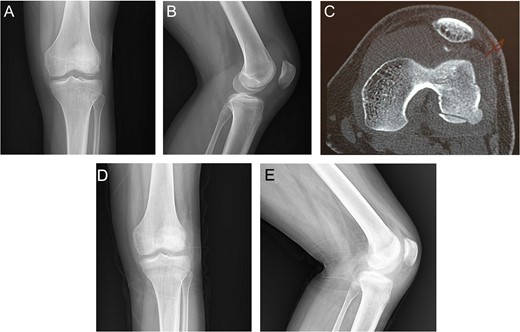

A 19-year-old male came with right knee pain and effusion after a non-contact injury of the knee during a football game. The knee had marked effusion with tenderness over the medial border of the patella. Radiography showed large OCF in the weight-bearing area of the lateral femoral condyle [Fig.1Aand B]. CT scan showed bony fragments from the medial border of the patella [Fig. 1C]. Three months after surgery, radiography showed complete healing of the injury with the full knee range of motion (ROM) [Fig. 1D and F].

Case 1. A and B Radiography showing lateral femoral condyle OCF. C, CT scan showing OCF and patellar avulsion fragment.D and E, 3 months postoperative radiography showing complete union.